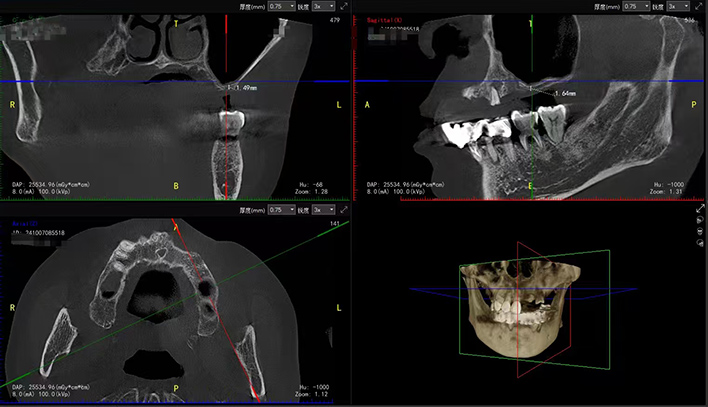

术前,医生会通过 CBCT(锥形束计算机断层扫描)精确测量牙槽骨量、评估上颌窦形态,并综合患者全身健康状况制定个性化手术方案。根据骨量情况,种植体可选择与提升术同期植入,或待骨组织愈合后二期植入。